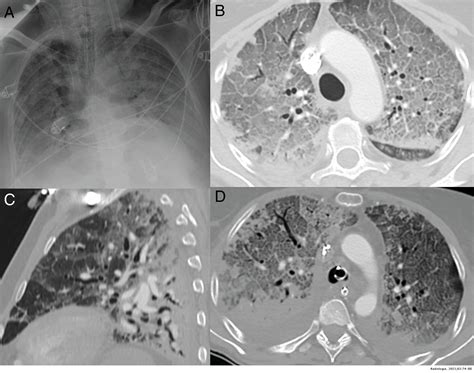

Se considera una manifestación cutánea sugestiva de COVID-19, al igual que la pseudo-perniosis. El exantema vesicular variceliforme aparece coincidente al resto de síntomas o dentro de las 2 primeras semanas, aunque también puede aparecer antes que las manifestaciones respiratorias de la COVID-19. Se han descrito dos formas de presentación diferentes: difusa y localizada.

La forma difusa es la más frecuente, consiste en lesiones polimorfas de pápulas, vesículas e incluso pústulas, con una distribución corporal generalizada, afectando incluso a las palmas y plantas. La forma localizada consiste en lesiones monomorfas más pequeñas, en el mismo estadio evolutivo, que suelen localizarse en el pecho y/o la espalda. No hay que confundir este tipo de lesiones con las reactivaciones de los virus herpes simple o zoster. Estas reactivaciones son relativamente frecuentes en pacientes con COVID-19 debido al estado de inmunosupresión relativa generado por la infección.

Exantema vesicular difuso en paciente COVID-19.

Las lesiones vesiculares en los exantemas virales se producen como consecuencia directa de replicación viral en el endotelio o en el queratinocito, hallándose partículas virales en el contenido de las vesículas.

No obstante, las pruebas de PCR para SARS-CoV-2 realizadas del contenido de las vesículas y de las biopsias de piel de estos pacientes son negativas. Debido a la falta de estandarización en la realización de los tests diagnósticos en muestras de piel no se puede descartar con seguridad la presencia del virus en estas lesiones. No obstante, de estar presente, la capacidad infectiva a través de las lesiones cutáneas sería baja.